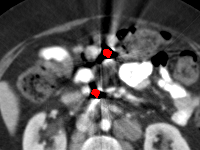

Effect of metal mask projection (SE0-Net vs SE-Net). From Table 1, we can observe the use of instead of improves the performance for at least 4.1 dB in PNSR and reduces MSE from 0.95219 to 0.00074 for all metal sizes. The groups with large metal implants benefit more than groups with small metal implants. As shown in Fig. 4, the artifacts in metal trace of SE0-Net are over-removed or under-removed, which introduces bright and dark bands in the reconstructed CT image. With the help of , SE-Net can suppress the artifacts even when the metallic implants are large and the surrogate data are more consistent with the correct data outside the metal trace.

Effect of sinogram padding (SE-Net vs SEp-Net). Sinogram padding mainly improves the performance in the group with the largest metal objects, with a PSNR gain of 0.15 dB and an MSE reduction of 0.00048. As shown in Fig. 4, the model with sinogram padding restores finer details of soft tissue between large metallic objects because more correct information is retained by periodic padding than zero-padding.

Effect of learning with (SEp-IE-Net vs Ours). When is jointly restored with the corrupted , the sinogram correction performance is affected with an increment of 0.00033 in MSE and of 0.7 dB in PSNR. More details of soft tissue around metal are retained and the image becomes sharper, as shown in Fig. 4.